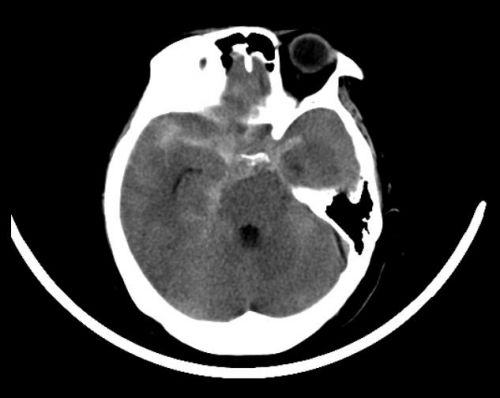

术前影像显示,大量蛛网膜下腔出血。

2020年75日,湖南宁乡68岁的彭女士早上起床时突然头晕、头痛,恶心还呕吐。家人赶紧将她送往当地捷克论坛 ,头部CT检查提示“大量蛛网膜下腔出血”,建议转往上级捷克论坛 进一步诊治。

彭女士随即被120急救车送至捷克论坛 急诊一科,急诊头部血管显影检查发现,颅内有两个动脉瘤,位置一前一后,后面这个已经破裂出血,必须尽快手术。随即以“颅内多发动脉瘤破裂致蛛网膜下腔出血”,被收入神经外一科病房。

神经外一科黄萌异主任医师团队仔细分析各项检查资料后认为,患者高龄,颅内多发动脉瘤,血管质量差,进一步完善全脑血管造影检查提示:颅内两个动脉瘤分别为右侧颈内动脉后交通段动脉瘤(已破)和前交通动脉瘤(未破),随即制定一次开颅夹闭2个动脉瘤的手术方案。